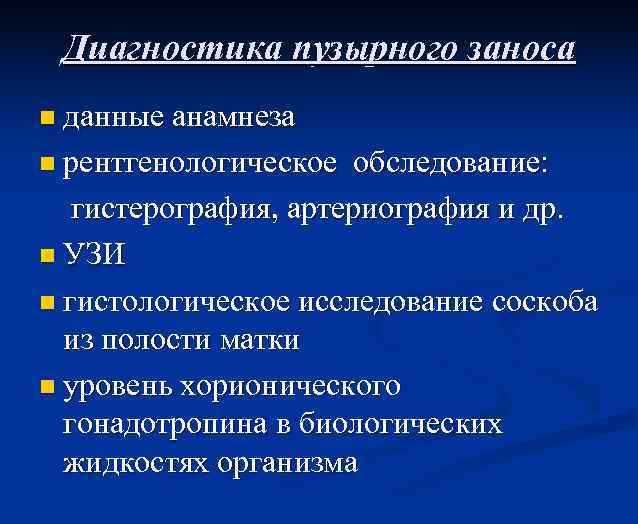

Диагностика пузырного заноса данные анамнеза n рентгенологическое обследование: гистерография, артериография и др. n УЗИ n гистологическое исследование соскоба из полости матки n уровень хорионического гонадотропина в биологических жидкостях организма n